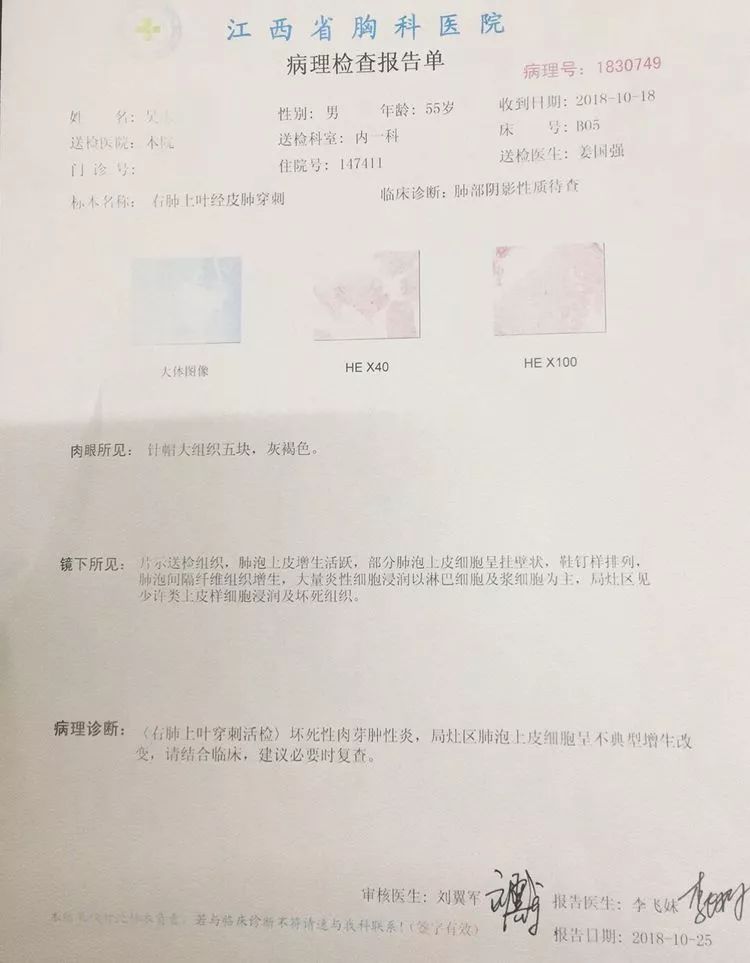

第三例 吴大伯今年55岁,右上肺后段结节样病变,伴有钙化,一般这种情况大家都会觉得是结核球。

由于患者门诊抗结核治疗病灶稍增大,医生们经商议最终决定穿刺。虽然从影像看起来没有穿刺路径,不过没关系,省胸科医院经验丰富的内科医生们可以通过体位来调整。

待病理报告出来后告诉我们,结核是存在的,同时见不典型增生。

注意了,见不典型增生,就是癌前病变,但目前还不是癌,此时正是最佳手术时机,是可以治愈的!如果再晚一些时间,也许就没机会了!